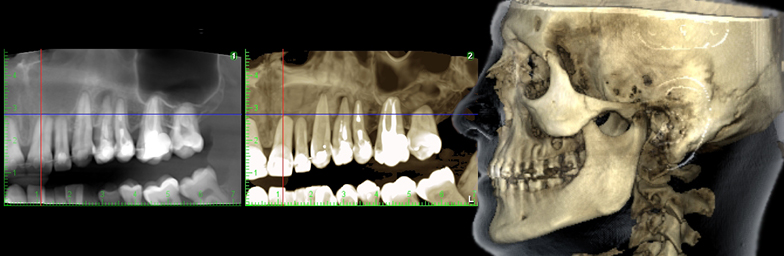

CBCT

CBCT-ul este o investigație radiologică modernă și frecvent utilizată în stomatologie, cu numeroase aplicații în chirurgia oro-maxilo-facială, ortodonție, parodontologie, implantologie, endodonție, ORL sau oncologie.

CBCT-ul este o investigație radiologică modernă și frecvent utilizată în stomatologie, cu numeroase aplicații în chirurgia oro-maxilo-facială, ortodonție, parodontologie, implantologie, endodonție, ORL sau oncologie.